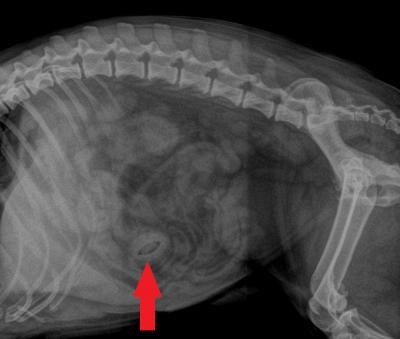

RTG břicha pejska, co pomáhal při zdobení dortu.

Pecka z broskve ve střevě způsobovala pejskovi bolesti břicha a úporné zvracení. Šipka ukazuje polohu cizího tělesa na RTG.